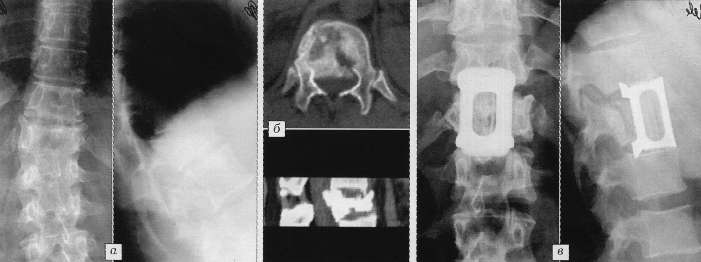

Рис. 1. Больной С. 47 лет.

а - рентгенограммы до операции: неполный взрывной перелом тела L1 позвонка,

кифоз 24°; б - стереотомограммы до операции: деформация позвоночного канала,

каудальная часть тела позвонка не повреждена; в - рентгенограммы через

1 год после корригирующего корпородеза, аутопластики и моносегментарной

эндофиксации. |

|

Рис. 2. Больная К. 47 лет.

а - рентгенограммы до операции: взрывной перелом тела Т12 позвонка, кифосколиотическая

деформация; б - компьютерная томограмма до операции: дислокация дорсального

фрагмента в позвоночный канал; в - рентгенограммы через 1 год после коррекции

кифосколиоза, передней декомпрессии, аутопластики, бисегментарной эндофиксации |